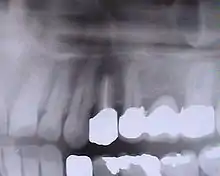

Implants en place. Notez qu'il y a moins d'implants que de dents sur la prothèse.

Prothèse totales fixes sur implants

Elles ont en règle réalisables sur six implants (selon des modalités bien précises pour l'observation desquelles le poseur d'implant doit avoir les qualifications requises). Selon la récession osseuse du patient à la suite de la perte de ses dents, on réalisera une prothèse sans ou avec fausse gencive. Moins coûteuses que les bridges, ces prothèses sont moins longues à réaliser. Rien n'empêche cependant le patient de faire remplacer sa prothèse résine par une prothèse céramique après une période d'observation de deux ans.